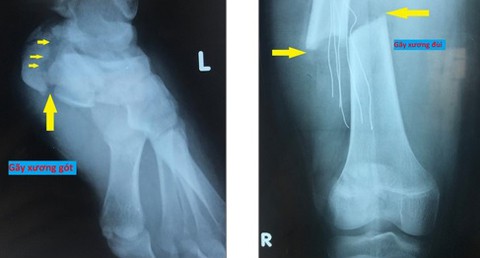

Kết quả hình ảnh chụp cắt lớp và cộng hưởng từ cho thấy bệnh nhi bị gãy xương đùi phải, gãy xương gót chân trái, gãy xương hàm trên và hàm dưới, tổn thương mô mềm vùng mặt.

Kết quả hình ảnh cho thấy bệnh nhi bị gãy xương đùi phải, gãy xương gót chân trái

Các bác sĩ đã hội chẩn và tiến hành phẫu thuật kết hợp xương đùi phải và xương hàm mặt. Bệnh nhi sau đó được theo dõi tại khoa hồi sức tích cực.